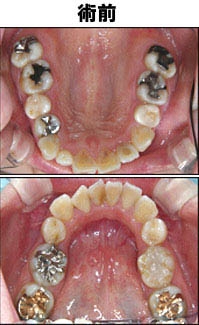

M・A様 女性 33歳 セラミックインレー

術前→術後

Aさんは、奥歯の詰め物の歯と歯の間の部分が段差になっていたのを修正するために治療しました。歯と歯の間の部分はぴったりあわせるのが難しい部分なのです。しかし、ただでさえ汚れを取るのが難しいところなので、清掃しやすいように段差がなくスムーズにするため、細心の注意を払って治療しました。

以前は保険の金属で詰めてありましたが、今回はセラミックの詰め物を選択されました。左のページの写真を見ていただければわかるように、とてもきれいに仕上がります。パッと見ただけでは自分の歯と区別できません。この自然な仕上がりとプラスチックのように変色・磨耗をしないので、この見た目がいつまでも続くこと、しっかりとした咬み合わせを長期間維持できることがセラミックの大きな特徴です。